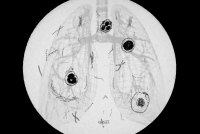

Possibility of Wildlife-to-Human Crossover Heightens Concern About Chronic Wasting Disease

A response is ramping up to a potential spillover of the neurological disease to humans from deer, elk, and other animals.